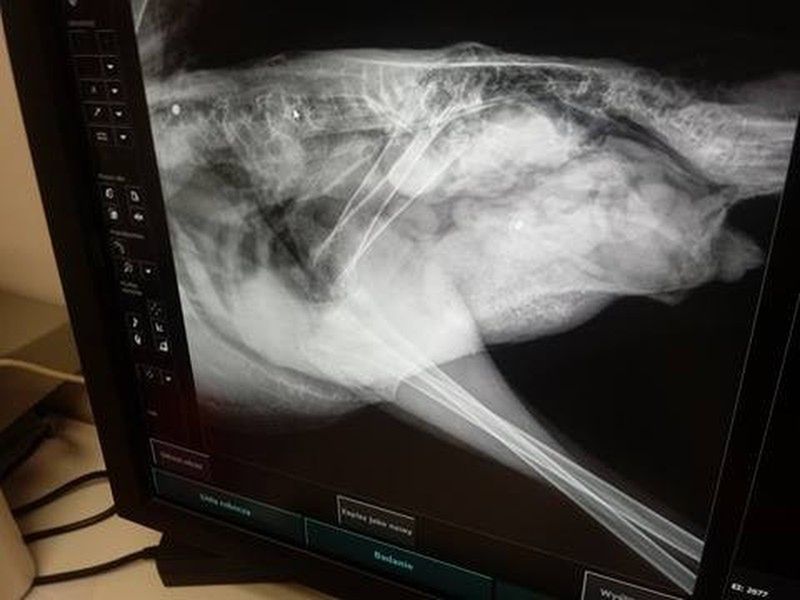

Zwierzę przewieziono do kliniki we Wrocławiu. Tam prześwietlenie ostatecznie pokazało, że śrut utkwił zwierzęciu w kręgosłupie.